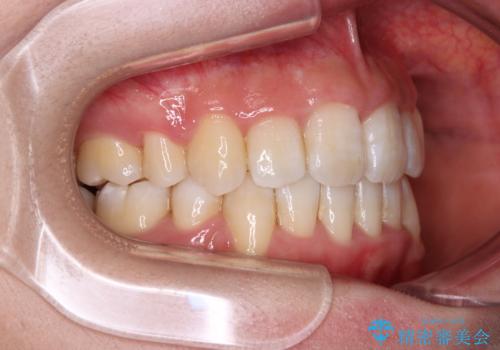

デコボコの解消で歯が磨きやすくなり、抜歯矯正により口元の突出感が大幅に改善され、スッキリした口元になりました。